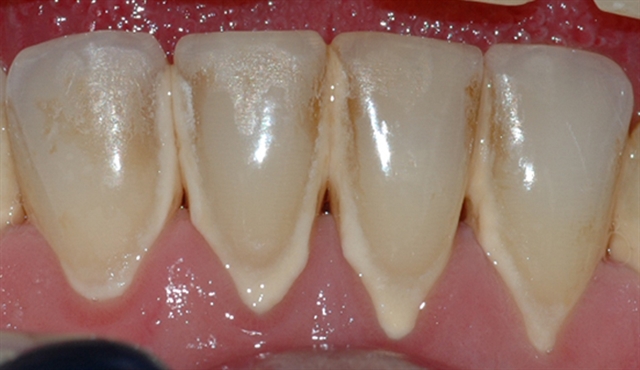

• Biletet viser eit tannsett med synleg tannstein og misfarging.

• Biletet viser eit nærbilete av tennene i underkjeven med tannstein og misfarging.